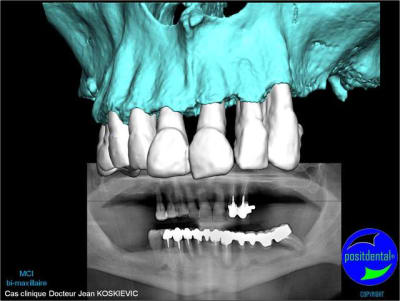

Je viens de recevoir les empreintes pour réaliser un Positscan en prévision d'une MCI bi-maxillaire. "chouette" un peu de métal pour corser l'histoire.

rendu 3D maxillaire sup, pano et photo

3D maxillaire inférieur et photo

Montage esthétique ou wax-up 3D